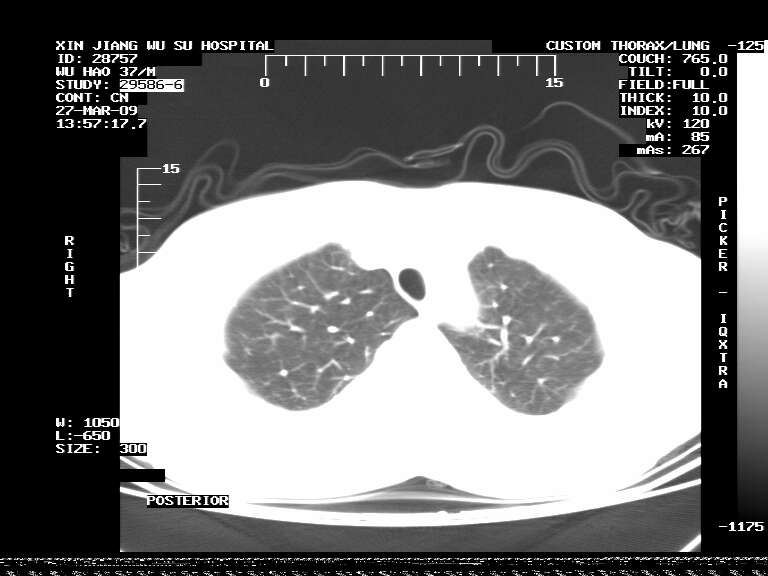

男,37岁,体检胸透发现阴影。

患者体检发现 无症状 左肺下叶占位,边缘模糊,可见血管聚束、分叶、胸膜牵拉,增强呈不均匀性强化。 首先考虑左肺下叶周围型肺癌,建议穿刺活检。

患者体检发现 无症状 左肺下叶占位,边缘模糊,可见血管聚束、分叶、胸膜牵拉,增强呈不均匀性强化。 首先考虑左肺下叶周围型肺癌,建议穿刺活检。支持!

左肺下叶见一结节病变,边缘欠清不光滑,与胸膜粘连且胸膜局限性增厚,注药后呈环形强化,动脉期壁呈明显点环状强化,静脉期壁强化减低,中心密度低无强化,灶周无明显的卫星灶和水肿区(晕征)---考虑周围性肺癌,不除外感染性病变,建议穿刺活检。